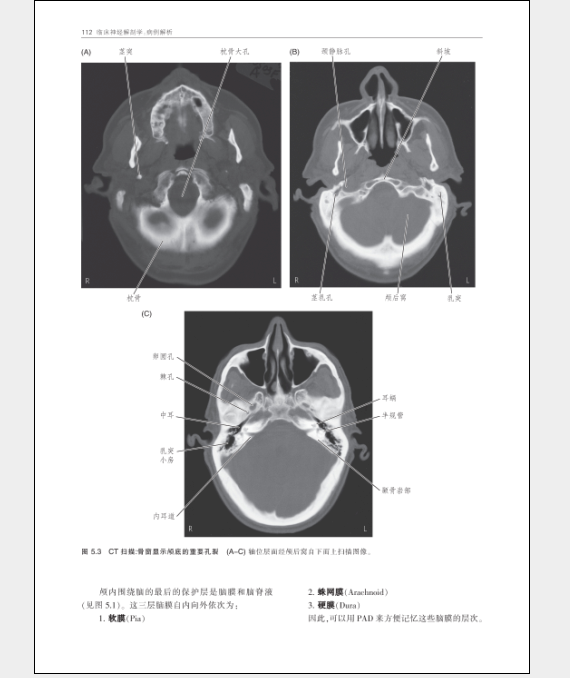

第5章保護中樞神經系統的骨性結構和被膜